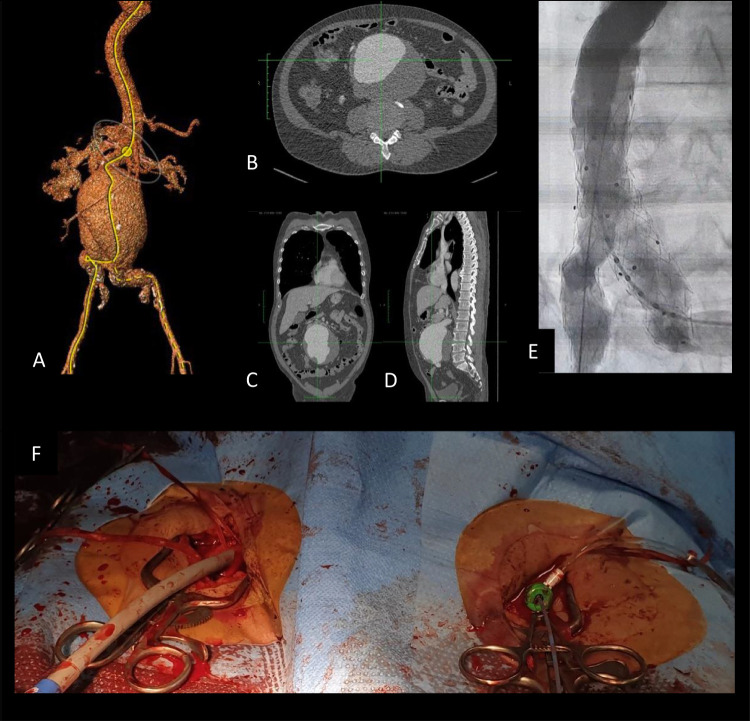

Case: A 65-year-old male with a history of endovascular abdominal aortic aneurysm repair (EVAR) developed left acute limb ischemia (Rutherford category III) and abdominal pain. A CT scan showed significant gas formation around the endograft and complete occlusion of the left distal iliac artery to the femoral arteries. Despite undergoing hip disarticulation and wound care, aortic endograft removal was not possible due to a lack of replacement grafts. Microbiological cultures from arterial pus and urine identified multiple antibiotic-resistant extended-spectrum beta-lactamases (ESBL) producing Escherichia coli. Histopathological analysis of the common femoral artery specimen indicated chronic medium-sized arteritis characterized by endothelial erosion, fibrotic myocytes in the tunica media, and fibrosis of the adventitial layer with inflammatory cell infiltration. The patient succumbed in the ICU 6 days later due to uncontrolled sepsis.

导言:我们介绍了一例晚期内移植物感染病例,感染发展到左侧髂动脉和股动脉,导致左下肢坏疽,患者死亡:一名65岁的男性患者曾接受过血管内腹主动脉瘤修补术(EVAR),后来出现左侧急性肢体缺血(卢瑟福III级)和腹痛。CT 扫描显示内移植物周围有明显气体形成,左侧髂远端动脉至股动脉完全闭塞。尽管进行了髋关节离断术和伤口护理,但由于缺乏替代移植物,主动脉内膜移植物无法移除。从动脉脓液和尿液中进行的微生物培养发现了多种产生耐抗生素广谱β-内酰胺酶(ESBL)的大肠埃希菌。股总动脉标本的组织病理学分析表明,患者患有慢性中型动脉炎,其特征是内皮侵蚀、中膜肌细胞纤维化以及伴有炎性细胞浸润的临近层纤维化。6 天后,患者因败血症无法控制而在重症监护室死亡:讨论:尽管EVAR术后内移植物感染的发生率很低(发病率和死亡率为20%-75%),但其风险很大。感染来源通常是血源性的,源于泌尿道或呼吸道感染,感染延伸至后续动脉的情况非常罕见;感染可能会引起慢性动脉炎症,长期而言可能会导致血栓形成和肢体缺血。本病例强调的是手术后 3 个月出现的低度感染。诊断通常需要通过 CT 血管造影来检测主动脉周围气体或液体。处理高级别感染必须完全切除内移植物,并用抗感染的移植物替代:结论:EVAR术后的内移植物感染虽然罕见,但可能造成严重后果。根据症状和 CT 扫描进行早期诊断。对于高级别感染,移植物内膜移除是金标准疗法,EVAR术后持续随访对预防感染至关重要。